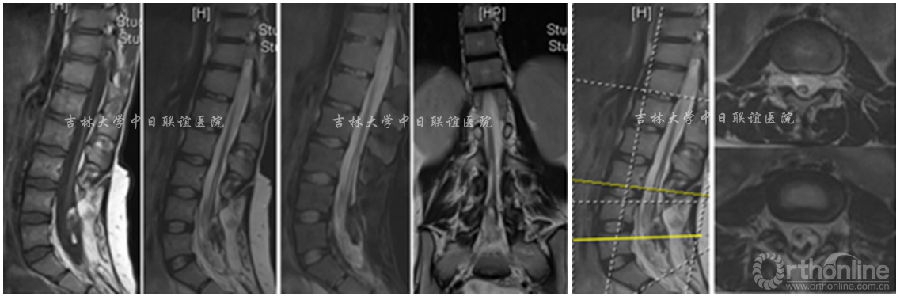

X线:L4—S5 脊柱裂。CT检查:L4-S5棘突及椎板缺失。腰椎MRI示:腰4-骶5椎板缺如,相应椎管内结构紊乱,脊髓末端与椎管内组织粘连固定于腰4椎体下缘,脊膜向外膨出,考虑脊柱裂伴脊膜膨出及脊髓栓系。

术前影像学检查: